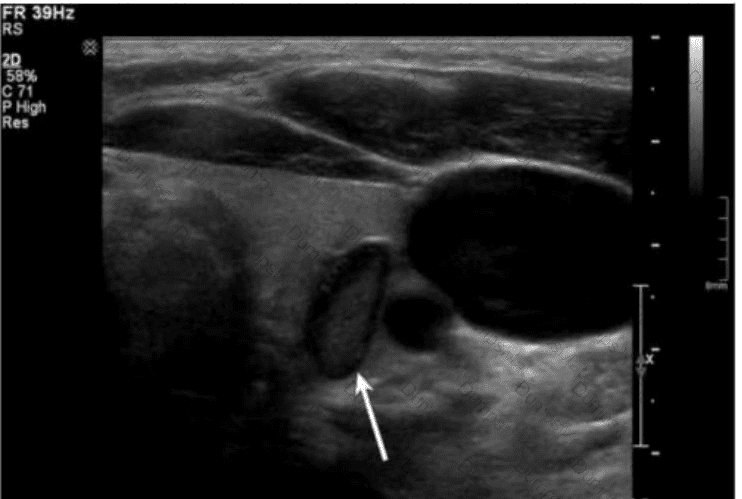

Questions 6

Which condition is most consistent with the sonographic appearance indicated by the arrows on this image obtained post thyroidectomy?

AB-Abdomen Question 6

Options:

A.

Recurring papillary thyroid cancer

B.

Normal postsurgical lymph node

C.

Residual glandular tissue

D.

Reactive lymph node

Buy Now